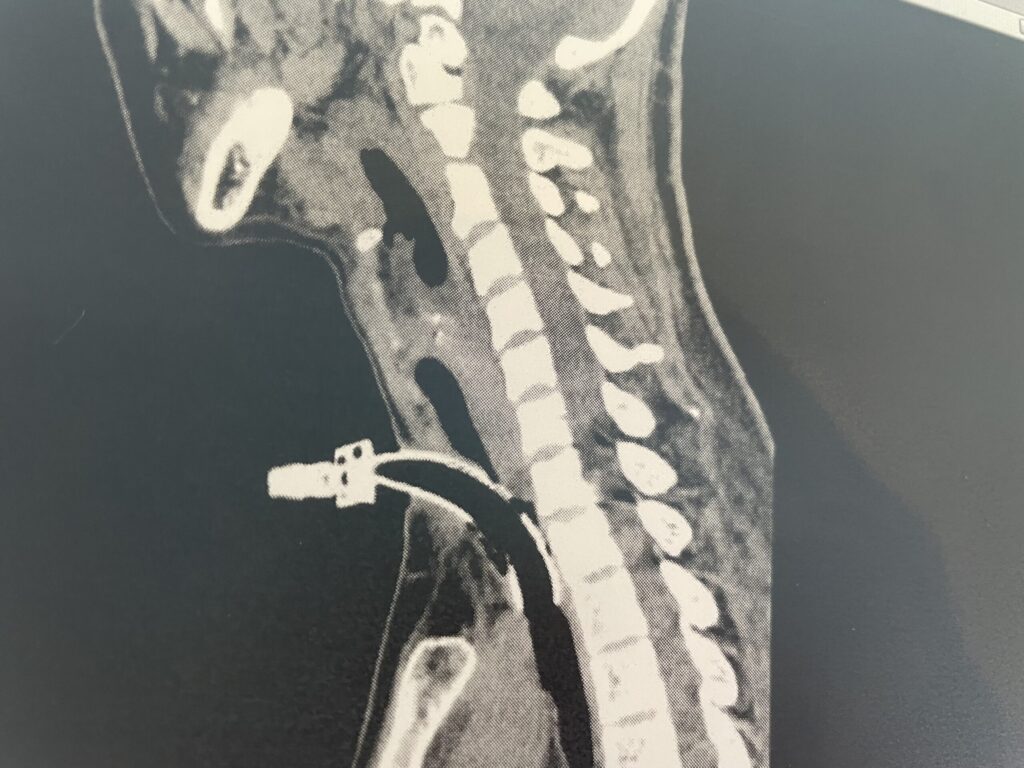

CT

最初、先生は、CTを撮るのは来週とか言っていたような。

気づいたら、CT検査という項目が増えている。

そして、いきなり呼ばれる。

さすがに、持続吸引なしで行くのは心配。

ということで、持ち込みの持続吸引器を付けていくことに。

酸素ボンベやら、点滴やら、吸引器やら。

ベッドに取り付けるものがいっぱいだ。

CTの撮影自体は、そんなに長くなかったけど、CT室で一度だけ吸引をしてもらった。

CTの結果

CTの後、すぐに先生がやってきた。

もうCTの確認してきたとか早いな。

「気切のカニューレが、気管にギチギチだわ。元々ちょっと気管が細いから、週明けに入れ直しすると思う」

そのせいか、カフもイマイチ膨らんでなさそうとのこと。

ただでさえ今日出血しているし、少し喉を休ませるために週明けの交換。

少し細めのに替える。

「あと、もうひとつ。肺にちょっと影がある。今すぐ抗生剤って感じではないけど、追加で肺の検査するかも」

その画像も見たかったなぁ。

「あ、ちなみに、脳には全く問題なかったよ。まぁ、心配してなかったし、心配してないとは思うけど」